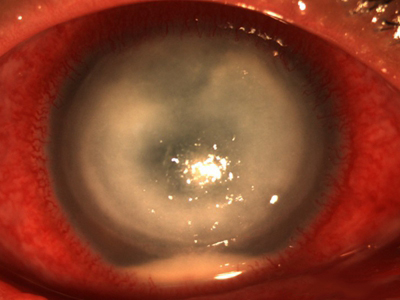

角膜挫伤角膜中间变成灰白色水肿浑浊图

角膜挫伤较为严重时,可见结膜发红,角膜中心处发白,整体浑浊水肿,此时有明显的疼痛感,伴流泪、畏光、视物模糊等表现。